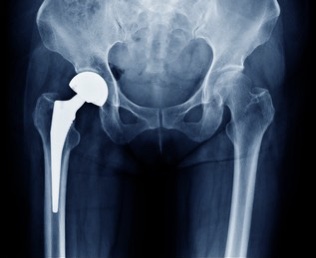

They took x-rays at this appointment and I was able to see my hip implant – that was pretty cool! I brought up my leg length discrepancy – although it has gotten so much better that I am not really worried about it. My PA did some measurements on my x-rays and assured me that if there is a difference, it is less than 1 mm which is the best that I could hope for. He tells me that my implant is the smallest they make without custom ordering one – a size 2. Who knew my hip implant would make me feel skinny? On the other hand, I am apparently small boned so there goes using being big boned as an excuse to be a little fluffy.